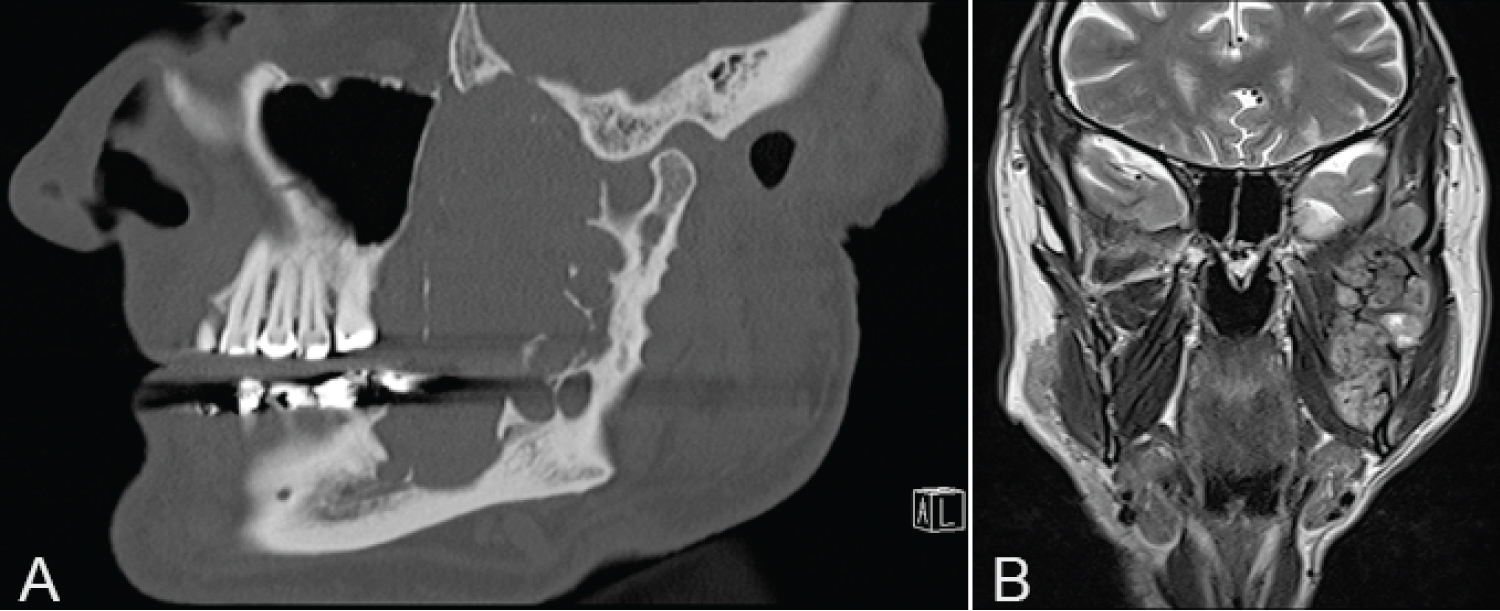

Orthopantomogram (OPG) showed a multilocular radiolucency expansile lesion of the left mandibular body to condylar region (Figure 1).

Figure 1: Panoramic radiographic view demonstrating multilocular radiolucency expansile lesion left mandible. View Figure 1

Computed tomography (CT) demonstrated a large 77 mm × 51 mm × 27 mm expansile osteolytic mass involving the left mandibular ramus, extending to the left mandibular body with multiple foci of cortical destruction and involvement of the interior alveolar nerve (Figure 2). On magnetic resonance imaging (MRI) the lesion was heterogeneous in signal intensity on both T1 and T2-weighted series, with extension to the masticator space involving the masseter, temporalis, lateral and medial pterygoid muscles. It abutted the deep surface of the parotid gland with no evidence of direct gland involvement and no evidence of perineural infiltration (Figure 3).

Figure 2: CT demonstrating expansile osteolytic mass (A) Axial view; (B) Coronal view. View Figure 2

Figure 3: MRI demonstrating lesion (A) Sagittal view; (B) Coronal view. View Figure 3